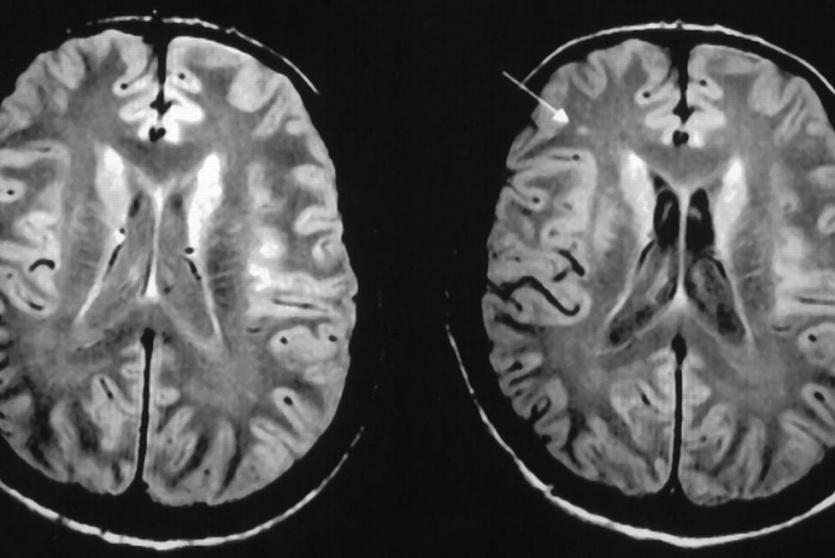

يتكون الدماغ بشكل أساس من مادتين، المادة البيضاء والمادة الرمادية، إذ يحتويان على مكونات بصورة مقسمة. لنتعرف على المادة البيضاء في الدماغ.

المادة بالبيضاء هي عبارة عن نسيج يغطي الأجزاء العميقة من الدماغ، يتكون من ألياف عصبية تسمى المحاور العصبية التي تربط ما بين الخلايا العصبية، تغطيها مادة دهنية تسمى غمد الميالين. (هو الذي يعطي المادة البيضاء لونها.)

تشكل المادة البيضاء حوالي نصف الدماغ، بينما تشكل المادة الرمادية (هو نسيج موجود على سطح الدماغ تعتبر القشرة الدماغية يحتوي على أجسام الخلايا العصبية، والتي تعطي المادة الرمادية لونها) النصف الاخر.